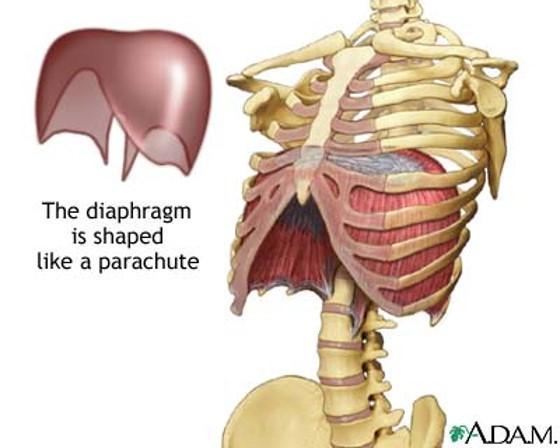

the diaphragm is the major muscle of ____________? contraction will "________" the diaphragm causing _________ changes that increase what into the lungs?

what is the diaphragm shaped like?

name 3 regions of the diaphragm?

parachute

sternal, costal and lumbar regions